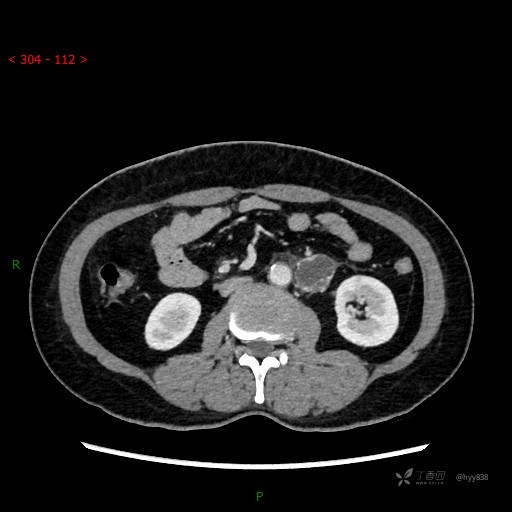

增强动脉期

CT平扫是外院的,因图像质量原因,不方便上传!